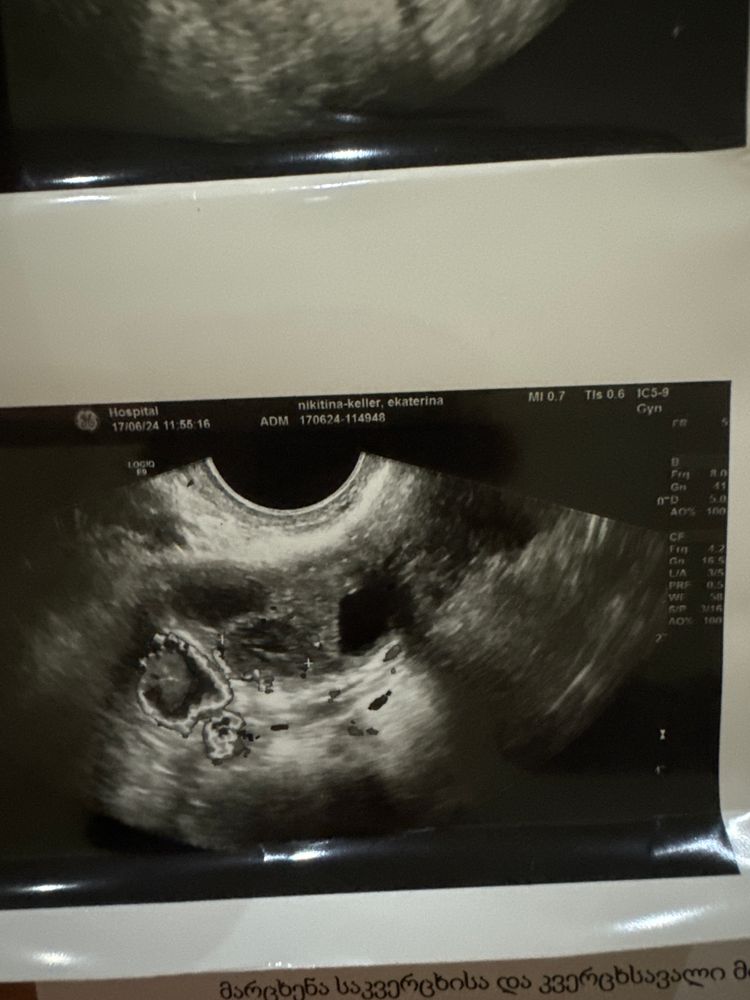

martamurder88, у меня была с месячными. Тоже шли 2-3 дня, потом тест +, бегу на УЗИ - ПЯ 4 мм. Было 4-5 недель. Обычная Б была. А это ПЯ справа повыше. Не там где крестики. Изображение

Узи на 13 день цикла Узи на 23д.ц